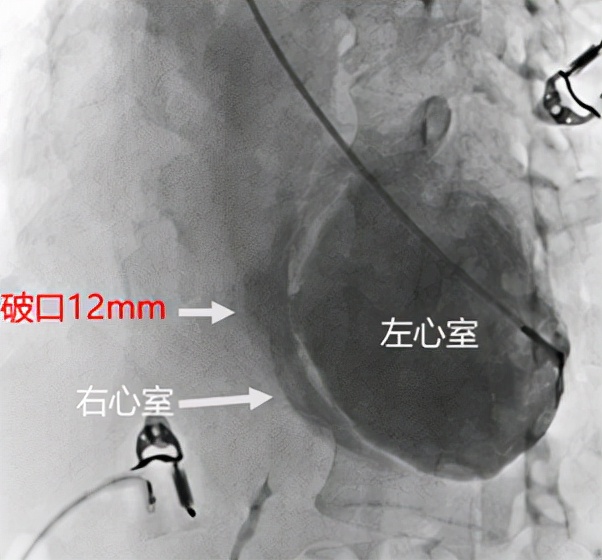

手术如期进行。鉴于患者病情严重,从股动脉入路进行相关操作有损伤主动脉内气囊反搏导管的可能性,故决定采用桡动脉入路。冠脉造影显示,患者前降支完全闭塞,张昌琳主任观察造影图像后认为可以通过介入方式开通闭塞血管。进一步行左心室造影显示,室间隔破口约12mm,右心室受室间隔压迫呈月牙状,测量肺动脉压力60/24mmHg,明显高于正常。

左心室造影显示室间隔存在巨大破口,测量直径约12mm,由于室间隔向右心室膨出,导致右心室受压,呈月牙状改变。